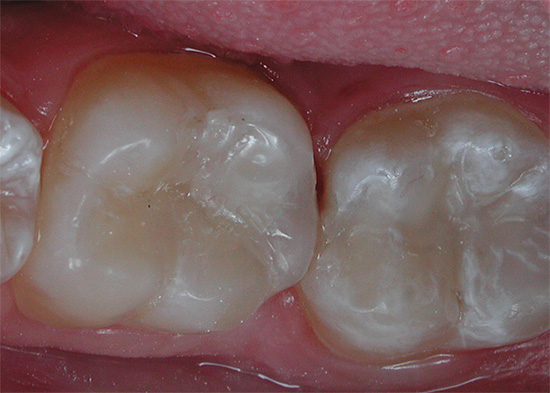

Bisogna capire che l'esposizione allo smalto dei denti e alla dentina con un trapano e, inoltre, la pulizia e il riempimento dei canali è una sorta di piccola operazione chirurgica per rimuovere i tessuti infetti e necrotici. È abbastanza naturale dopo la presenza di un lieve dolore - per il periodo di recupero del corpo.

I professionisti hanno determinati criteri in base ai quali il dolore dopo il riempimento può essere considerato come una condizione normale o, al contrario, come una certa deviazione dalla norma. Ciò tiene conto della dinamica del dolore, della sua natura, del livello di trattamento, della presenza di errori e complicanze durante esso e di altri fattori.